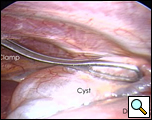

手術室では、全身麻酔と一つの肺換気の下で、胸腔鏡が右中顎線と第7肋間腔に導入された(下のビデオ1)。 嚢胞は、約9x6cmを測定し、右心膜の前外側の側面で容易に視覚化された(図3)。 嚢胞の後方に横隔神経を認めた。 第4肋間腔の前腋窩線に第二の切開を行った。 リングクランプを用いて嚢胞を把握した(図4)。 第5肋間腔の肩甲骨ラインに第三の切開が行われた。 胸腔鏡下はさみと焼灼術(心臓不整脈の可能性を最小限に抑えるために低い設定で)は、心膜から嚢胞を解剖するためにそのポートを介して使用された(図5)。 嚢胞と心膜腔との間の接続が同定された。 それは小さく、はさみで分割されました。 嚢胞の後面の解剖により除去が完了した。 横隔神経は常に明瞭に視覚化されていた。 病理報告では、良性の中皮内嚢胞の診断が確認されました(図6)。

| 図3.:心膜嚢胞の術中所見。 | 図4。 心膜嚢胞のリングクランプ収縮。 |